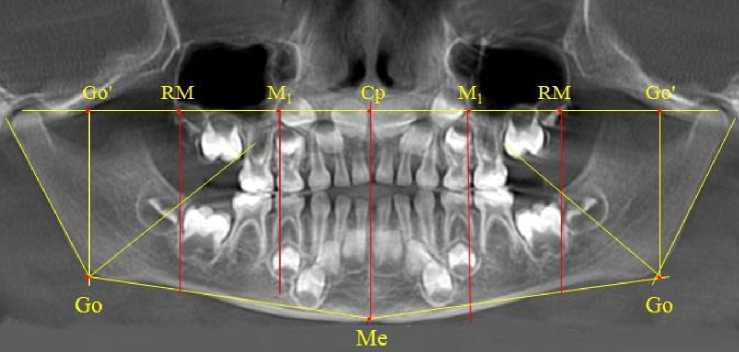

После полного замещения молочных зубов постоянными продолжалась минерализация и формирование корней постоянных премоляров, клыков и вторых моляров. Зачатки формирующихся вторых верхних постоянных моляров, так же, как и у детей предыдущей группы, располагались впереди ретро молярной вертикали (рис. 9).

Рис. 9. Рентгенограмма ребенка 12 лет после замещения молочных зубов постоянными

Биссектриса угла Cond-Go-Ме располагались позади от формирующихся зачатков вторых постоянных моляров нижней челюсти. После прорезывания вторых постоянных моляров происходило полное формирование постоянного прикуса. В этот период особенности рентгенологической анатомии, как правило, определялись наличием или отсутствием зубов мудрости (или их зачатков) в челюстных костях.

Наиболее благоприятной ситуацией считалось наличие 14 зубов на верхней и нижней зубной дуге (рис. 10).

На боковой рентгенограмме, так же, как и на ортопантомограмме, дистально расположенные зубы располагались впереди стресс-осей верхней и нижней челюсти (рис. 11). В подобных случаях определялось достаточная величина свободного пространства в ретромолярной области как на верхней, так и на нижней челюсти. Молярная вертикаль ограничивала молярную зону зубной дуги.

При наличии зубов мудрости на ортопантомограмме обращали внимание на положе- ние верхних зубов мудрости по отношению к ретромолярной линии, а нижних – по отношению к биссектрисе нижнечелюстного угла (рис. 12).